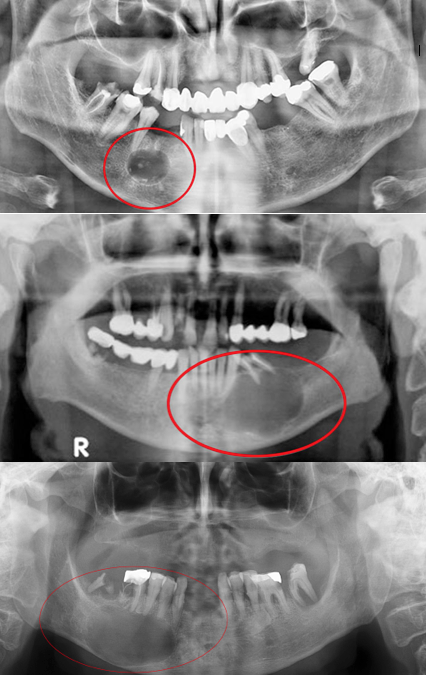

Οι πιο συχνές κύστεις των γνάθων είναι οι ριζικές ή ακρορριζικές κύστεις που εντοπίζονται γύρω από τα ακρορρίζια νεκρών δοντιών, με δεύτερη σε συχνότητα την οδοντοφόρο κύστη, που αναπτύσσεται κατά κανόνα γύρω από τη μύλη κάποιου έγκλειστου δοντιού, συνηθέστερα σωφρονιστήρα της κάτω γνάθου. Οι οδοντογενείς κερατινοκύστεις είναι η τρίτη συχνότερη κύστη των γνάθων και τις συναντάμε κυρίως στην κάτω γνάθο και στην περιοχή της γωνίας, αποκτώντας πολύ συχνά εξαιρετικά μεγάλες διαστάσεις, απωθώντας παρακείμενα δόντια ή προκαλώντας και απορρόφηση των ριζών τους. Η τάση τους να λαμβάνουν μεγάλες διαστάσεις, η πολύ μεγάλη συχνότητα υποτροπής μετά από αφαίρεσή τους, το πολύ λεπτό και εύθρυπτο τοίχωμά τους, η εμπλοκή τους στο σύνδρομο Gorlin και ο επιθετικός-διηθητικός τρόπος ανάπτυξής τους, καθιστούν τη βιολογική τους συμπεριφορά όμοια με εκείνη των καλοήθων νεοπλασμάτων. Έτσι, η Παγκόσμια Οργάνωση Υγείας στην τελευταία της αναθεώρηση κατατάσσει τις κερατινοκύστεις στους καλοήθεις οδοντογενείς όγκους των γνάθων μετονομάζοντας τη βλάβη σε Οδοντογενή Κερατινωσικό Όγκο.

Οι μη οδοντογενείς κύστεις είναι σπάνιες κύστεις, με τις γναθοσφαιροειδείς να εμφανίζονται χαρακτηριστικά ανάμεσα στις ρίζες του άνω πλάγιου τομέα και του κυνόδοντα τις οποίες και απωθούν, τις ρινοϋπερώιες στο πρόσθιο τμήμα της υπερώας στον ομώνυμο πόρο και τις ρινοχειλικές με εξωοστική εντόπιση κάτω από τη ρινοχειλική αύλακα.

Ακτινογραφικά οι κύστεις των γνάθων εμφανίζονται ως οστικές διαυγαστικές αλλοιώσεις με σαφή όρια αφοριζόμενες με χαρακτηριστική λεπτή ακτινοσκιερή περιφερική πύκνωση από το πέριξ φυσιολογικό οστό.